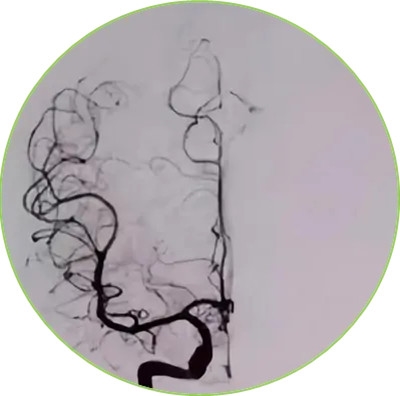

DSA图像

就好比给脑血管拍了张照片,清晰明了,根根分明。